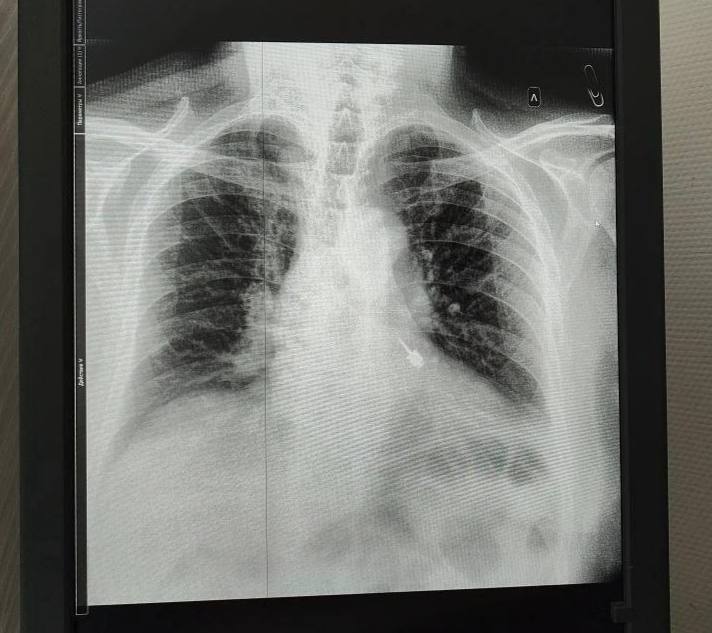

Диагностика подтвердила наличие инородного тела в левом бронхе. Медики провели экстренную операцию, учтя возраст и возможные риски. Благодаря слаженным действиям пациента удалось спасти.